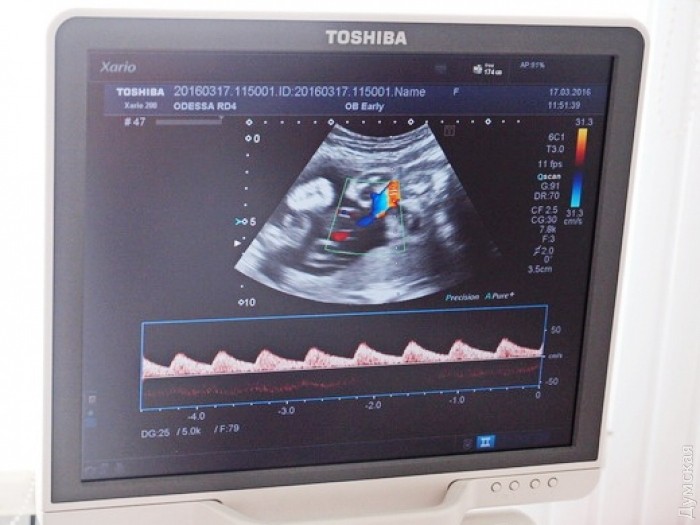

Одесский городской родильный дом №4, обслуживающий население Суворовского района, в рамках муниципальной целевой программы «Здоровье» получил новую ультразвуковую систему эксперт-класса японского производства. Как сообщили в мэрии, оборудование куплено за счет средств городского бюджета Одессы. Новый УЗИ-сканер современного образца обеспечивает высокую детализацию картинки и позволяет получить объемное изображение плода и всех его внутренних органов. Кроме того, аппарат имеет уникальный улучшенный режим визуализации кровотока, что позволяет использовать его для допплерографии как поверхностных, так и глубоких сосудов с очень высоким пространственным и временным разрешением. Новая ультразвуковая система позволяет своевременно и точно диагностировать врожденные пороки развития и нарушения в состоянии здоровья плода. Это позволяет медикам провести коррекцию ряда функциональных нарушений в ходе беременности, выбрать оптимальную тактику родоразрешения и дальнейшего оказания медицинской помощи ребенку. Беременные женщины с выявленными нарушениями берутся под усиленное диспансерное наблюдение врачей акушерско-гинекологической службы. СМЕРТЬ РОСІЙСЬКИМ ОКУПАНТАМ! Помітили помилку? Виділяйте слова з помилкою та натискайте control-enter |